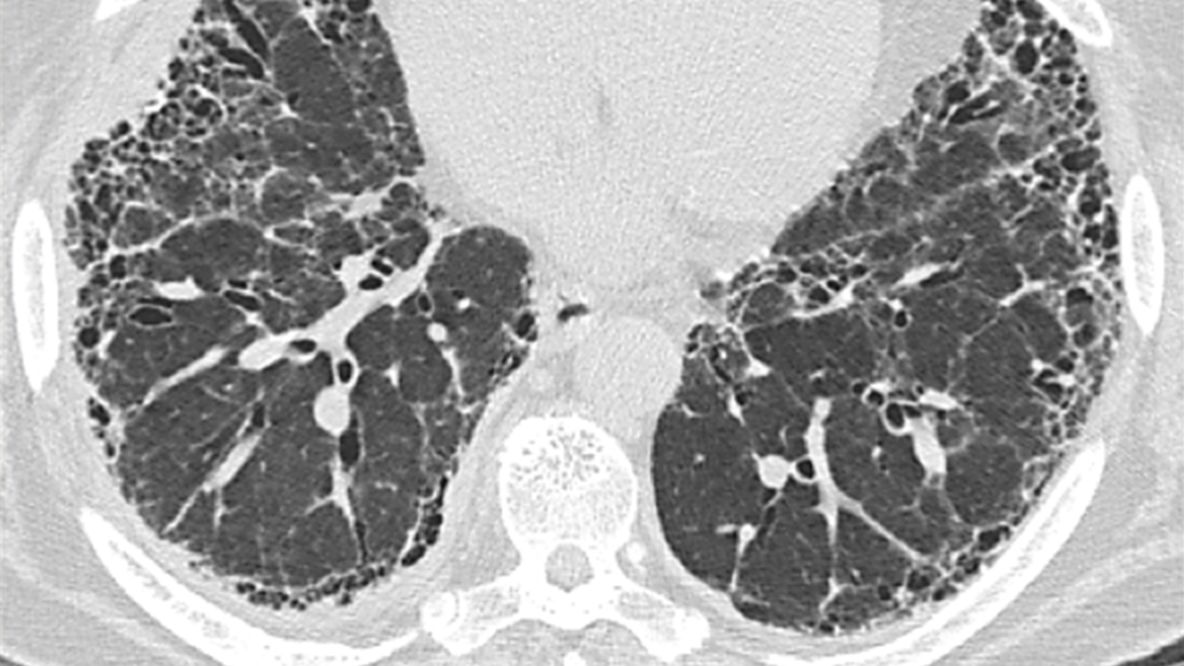

Caracteristicile compatibile cu un model UIP pe HRCT includ:9

• Aspect de fagure de miere

• Reticulații

• Bronșiectazii de tracțiune

HRCT

(opacități cu aspect de sticlă mată; opacități reticulare predominent în zonele pulmonare inferioare; micronoduli; condensare; aspect minim de fagure de miere)16

Pacienții cu PH fibrozantă prezintă în mod specific reticulații, bronșiectazii de tracțiune și pierderea volumului pulmonar, cu sau fără aspect de fagure de miere pe HRCT20